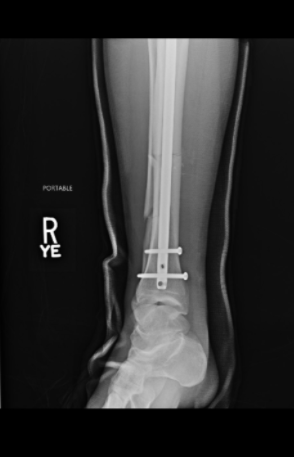

A través de su cuenta de Twitter, el artista marcial compartió imágenes del proceso que se llevó a cabo para reconstruir su pierna. En ellas se pueden ver la barra de titanio que se le dejó para afirmar sus huesos, además de los tres tornillos que fijaron la placa.

Weidman terminó con un fierro y tres tornillos. Foto: Twitter